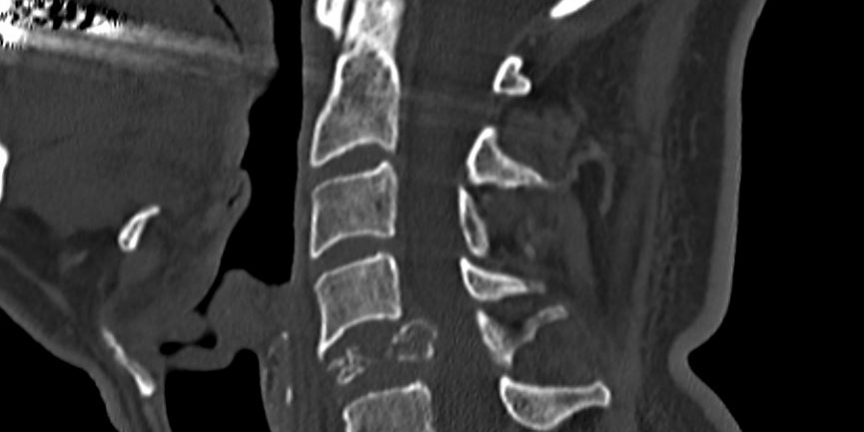

Παραγαγγλίωμα Α5 Σπονδύλου – Σωματεκτομή